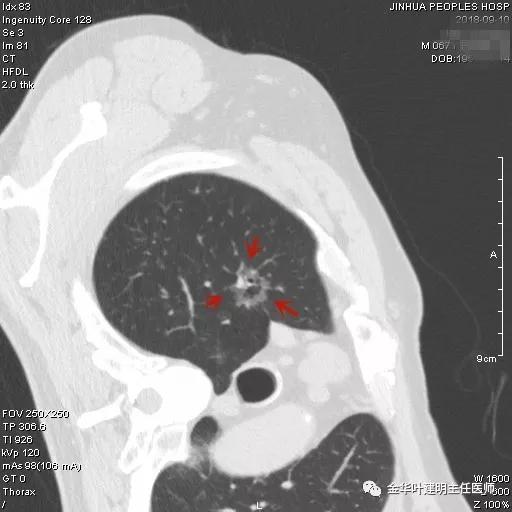

阚某是本院一护士的亲戚,遂找到胸外科叶建明主任医师会诊阅片,考虑是不是肺癌,要不要手术及靶扫描,以及如果需要手术,何时为宜?叶建明仔细阅片并与谭海栋副主任医师商量后,认为其右上肺磨玻璃结节是较为典型的浸润性腺癌影像表现,且与正常肺组织之间并不是界限清楚的,而是呈浸润性改变,但实性成分目前仍不明显,考虑为浸润性腺癌贴壁生长型或腺泡型可能大,应该进一步完善胸部CT靶扫描,以观察病灶细节。手术是要做的,手术方式的确定等靶扫描之后再定。以下为靶扫描影像:

以上诸图示右上叶病灶,是典型的腺癌影像,直径约2.5厘米许